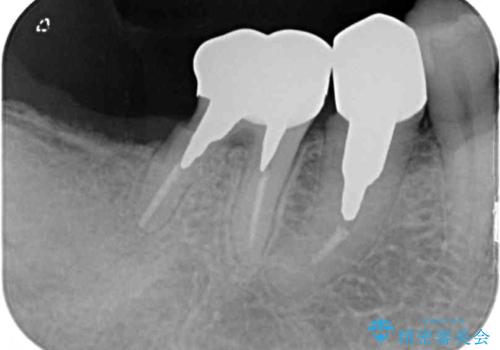

抜歯をしてから長年経過しており、レントゲンからは十分に骨があることが分かっていたため、速やかに治療を開始することとしました。

通常、奥歯を抜歯した状態で長年放置すると、咬み合う歯が伸びてきて、咬み合わせが乱れてしまうことが多いです。そのような場合には、部分的な矯正治療などが必要となるのですが、こちらの患者様は幸運なことに咬み合わせが乱れていなかったため、インプラント埋入から速やかに補綴治療を行うことができました。